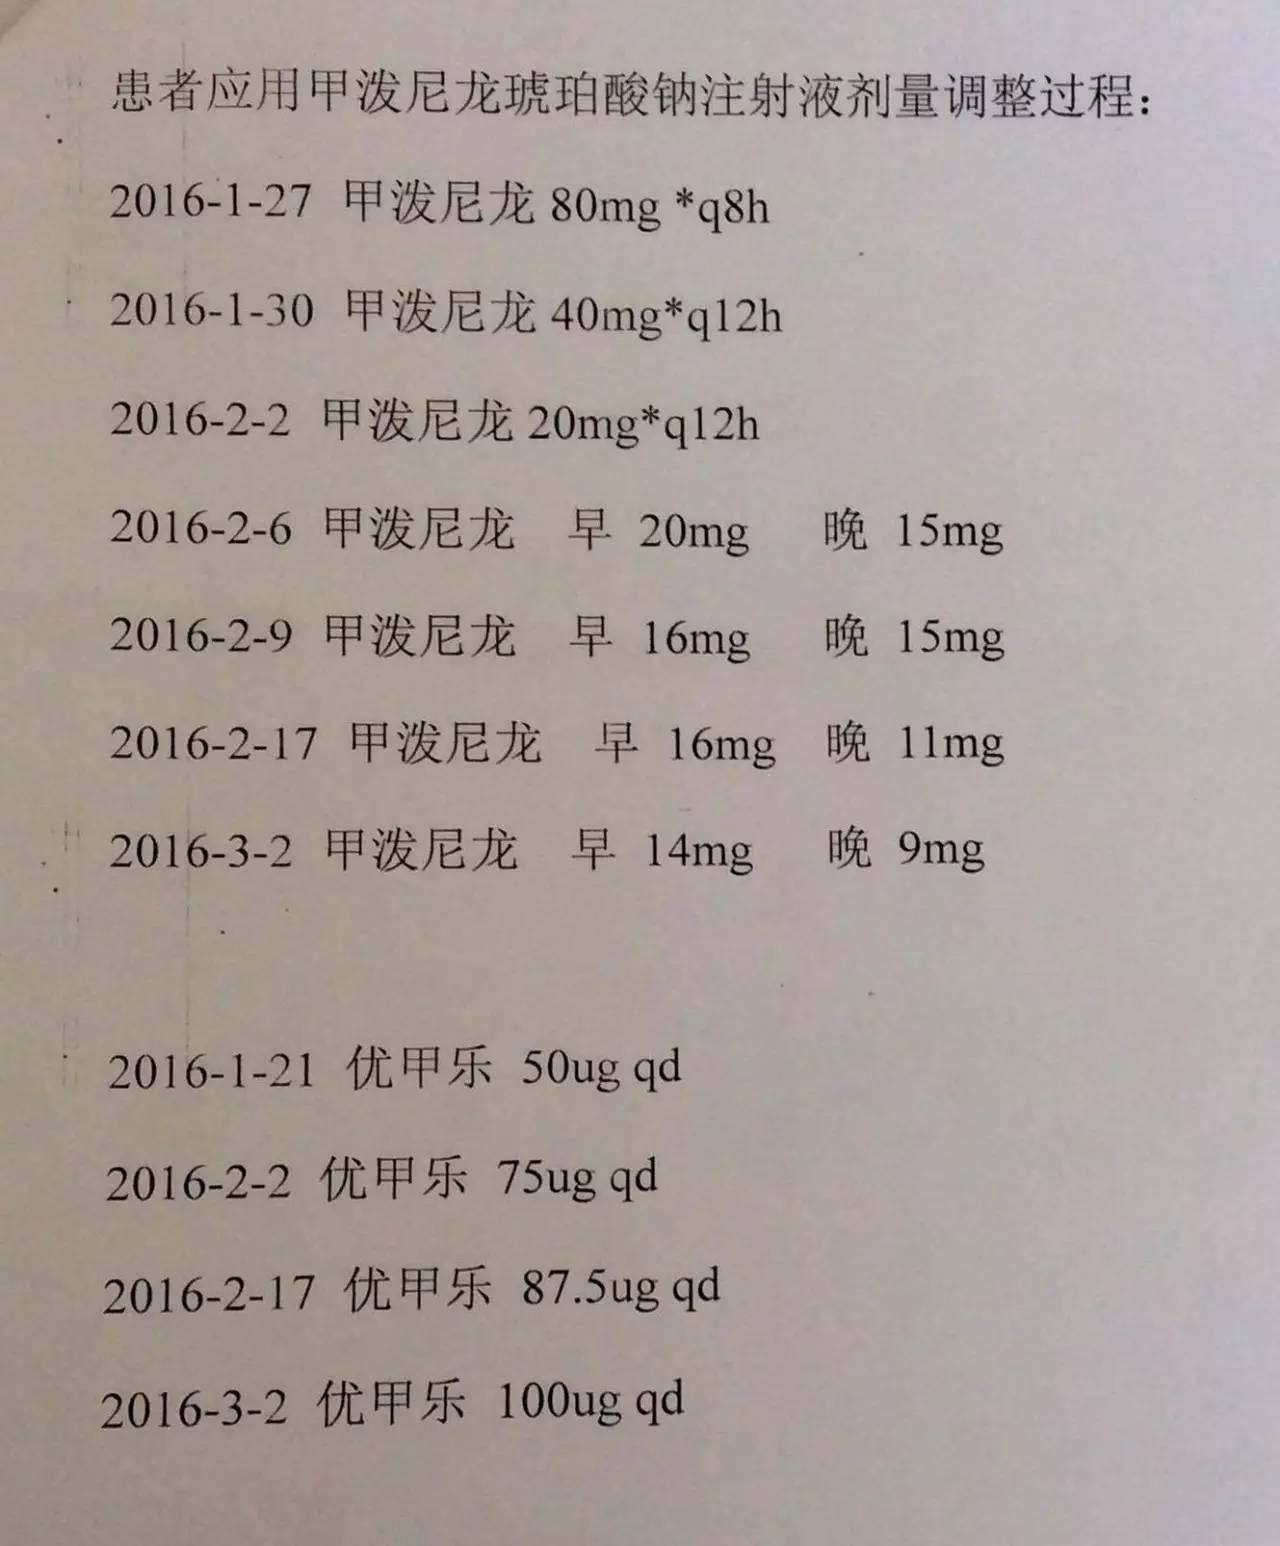

1.甲状腺功能减退症:因为患者属于继发性甲状腺功能减退症,因此根据FT4水平来调整优甲乐的剂量即可,目前加量到100μg/天,同意这种调整;

2.患者应用甲强龙,当时是因为出现了休克为了抢救所用,目前情况明细好转,可以每周(也就是贵院内分泌大夫会诊的7~10天)减量甲强龙1片(4mg); 但因为患者可能存在继发性肾上腺皮质功能减退症(继发于希恩综合征),减量到全天2片时需要评估清晨未服药前ACTH和血皮质醇、电解质、性腺激素六项来评估是否能够完全停药,还是需要减成替代剂量,此时可以应用泼尼松来替代甲强龙,泼尼松一片是5mg,等效于甲强龙1片,4mg,如果确实出现肾上腺皮质功能减退,可以逐渐减量到泼尼松全天1片(2.5mg,早上和下午各服用一片)。到时候再根据患者复查的情况判断肾上腺功能的恢复情况。